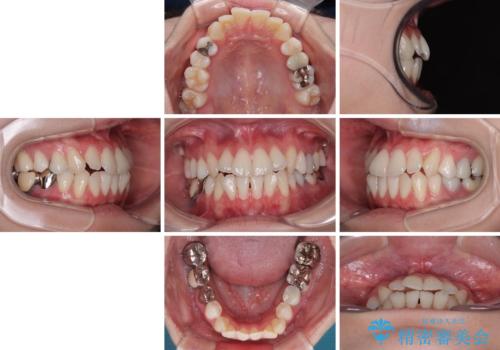

- 上下前歯のデコボコとクロスバイトを気にして来院された患者様です。

治療済みの処置歯が多いため、インビザラインを用いて矯正治療を行うこととしました。

下顎臼歯部にブリッジが装着されており、移動不可のため、IPR(歯と歯の間を削る)と歯列全体を拡大させることで、歯並びを整えていくこととしました。

インビザライン特有の奥歯の噛みにくさが治療後半に発現しましたが、無事に終了させることができました。